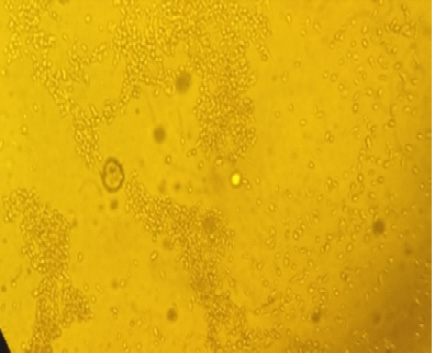

Figure 1

Normal Vero cells showed by inverted microscope